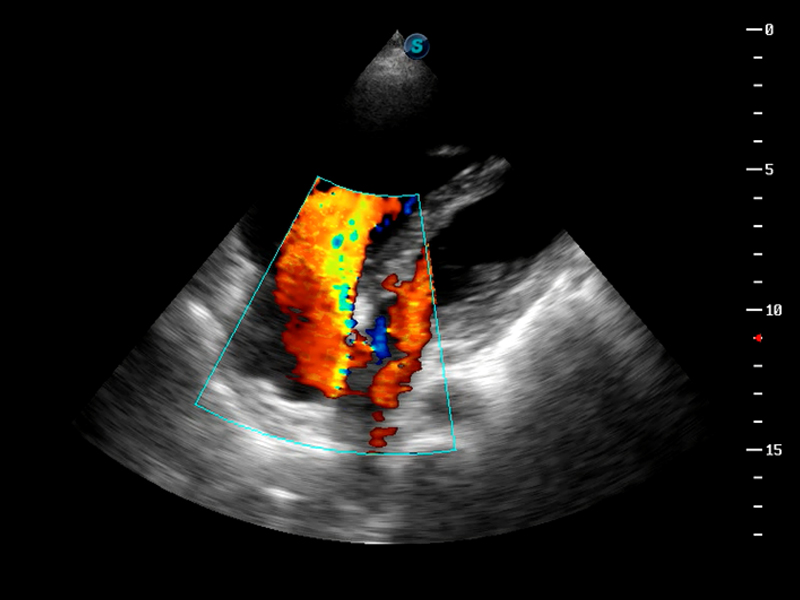

S9便携式彩色多普勒超声诊断仪是16877太阳集团研发的高端便携彩超设备,外观设计新颖、产品性能卓越。S9在便携超声领域采用了突破传统的触摸屏交互设计,并以先进的软件硬件技术和设计理念,为您带来清晰的图像质量、稳定的工作性能和便捷的操作体验。